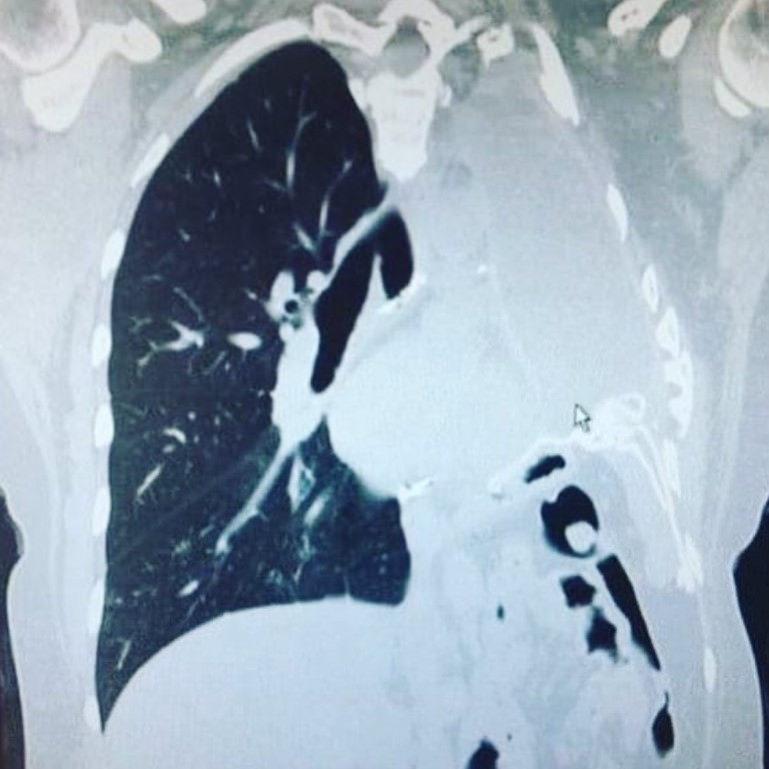

Yapılan tomografi sonucu akciğerine yakın bir bölgede tümör tespit edildi ve plevral mezotelyoma teşhisi kondu.